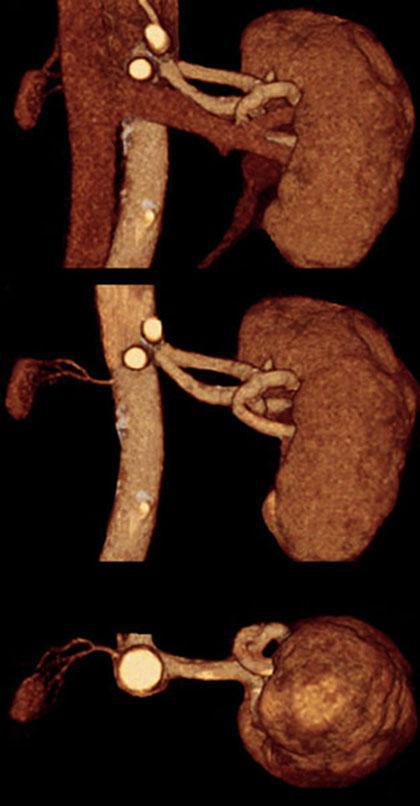

Hipoplasia renal 1